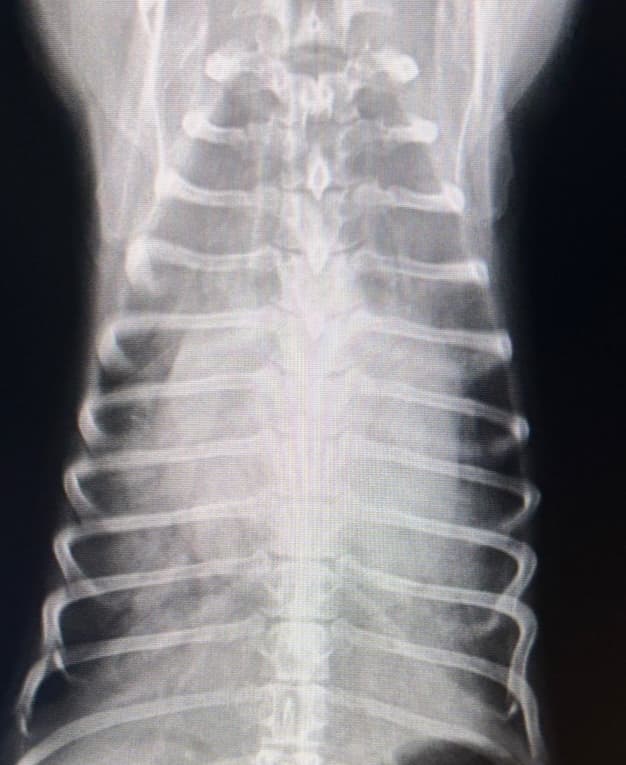

動脈管開存症とは犬の先天性心疾患で最も多いとされる病気です。産まれる前の胎児期にはたらいていた、大動脈と肺動脈をつなぐ動脈管という血管が遺残してしまうことで全身に行くはずの血液が肺動脈へと流れ、肺静脈や肺に過剰な負担がかかります。聴診で特徴的な雑音が聴取され病気が見つかることもありますが、確定診断にはエコー検査を用います。初期は無症状のこともありますが、重症化すると、疲れやすい、咳をする、呼吸が苦しいなどの症状が見られます。自然に血管が塞がることもありますが、症状が強い場合は手術で血管を塞ぐ必要があります。子犬に気になる症状がある場合は、ご相談ください。

獣医師 新井